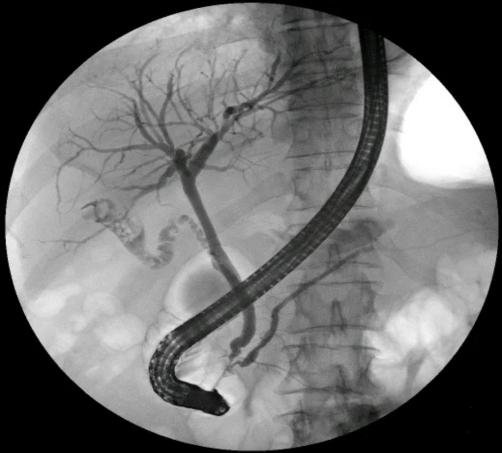

入院后,医疗团队为胡先生进行了全面检查。结合外院MRCP(磁共振胰胆管成像)结果及本院体格检查,确诊其为“胆总管结石伴胆管炎”。考虑到传统开腹手术创伤大、恢复慢,经综合评估,普通外科二病区团队决定为其实施更为微创的ERCP(经内镜逆行胰胆管造影)联合手术。

“手术包括内镜下乳头括约肌切开、胆管扩张、结石取出及鼻胆管引流等多个精细步骤,对操作技术要求极高。”手术团队介绍,手术需在内镜引导下精准定位并取出结石,同时避免损伤周围组织。10月23日,团队凭借丰富经验与娴熟技术,成功为胡先生完成手术。术后患者恢复良好,腹痛消失,无并发症,于术后第三天康复出院。

ERCP,即经内镜逆行胰胆管造影,是将带摄像机的十二指肠镜经口腔、食道送入十二指肠,再通过十二指肠乳头向胆管或胰管注入造影剂,借助X线摄片清晰显示胰胆管系统,同时完成诊断与治疗的技术。

• 通过造影清晰呈现胆管、胰腺导管的解剖结构与病变位置,让“看不见的病灶”变“清晰可见”;